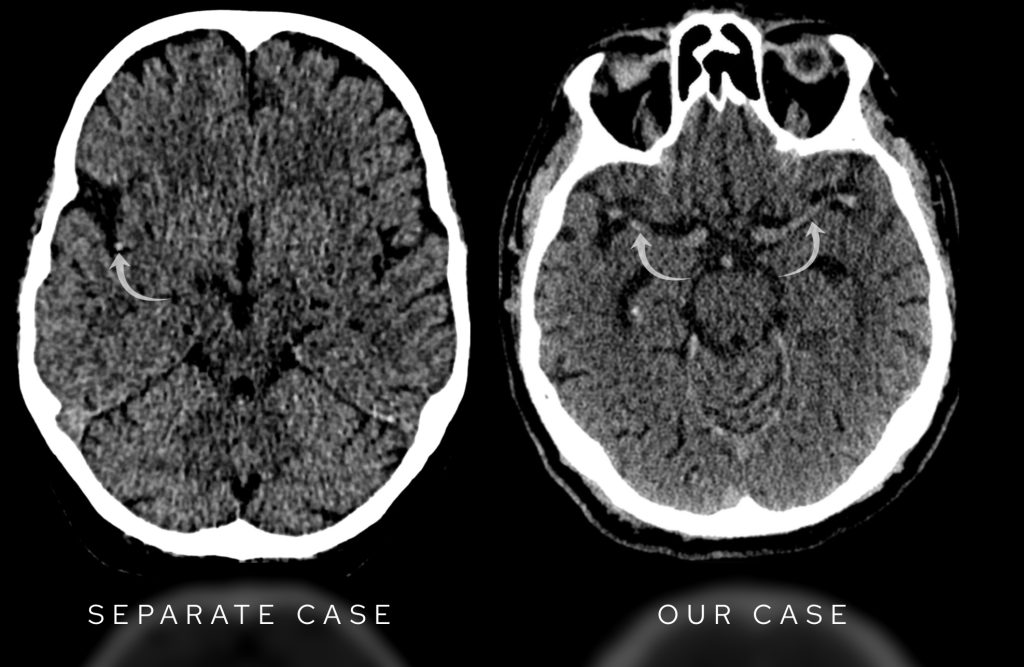

Going back to our case on the right sided image below, looking at both middle cerebral arteries, they appear equal in density, so there is no hyperdense MCA sign present.

On the left we have an example of a positive right sided hyperdense MCA in a case of acute stroke. In our case on the right sided image, the middle cerebral arteries are equal in density and considered normal.